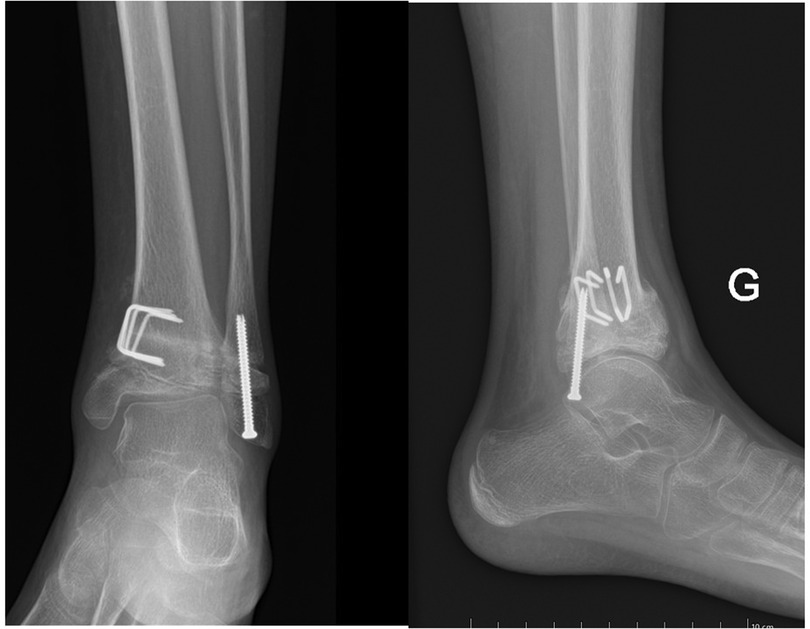

Despite this, however, the patient noted no relief from pain. Even though joint function was preserved, marked functional pain persisted. As a result, surgical treatment was suggested to the boy's parents, and they gave their consent. The treatment started with a diagnostic arthroscopy of the left ankle; during the arthroscopy, we noted irregularities and fissuring in the articular cartilage of the distal tibia, but there were no mobile fragments or intra-articular loose bodies. Then a 13° distal tibial medial varisation osteotomy with bone subtraction (7 mm) was realized to correct the valgus, and a complementary epiphysiodesis was performed at the level of the distal tibia by drilling carefully the medial aspect of growth plate under radiographic guidance. A distal fibular epiphysiodesis was also performed by multiple direct drilling of the physis and by inserting a fully threaded screw through the growth plate (Figure 4).

Figure 4. This final postoperative x-ray shows the left ankle after an arthroscopy that had revealed irregular joint cartilage and the subsequent osteotomy of the left tibial metaphysis to correct the varus with an additional epiphysiodesis of the distal tibia and a complete epiphysiodesis of the distal fibula.